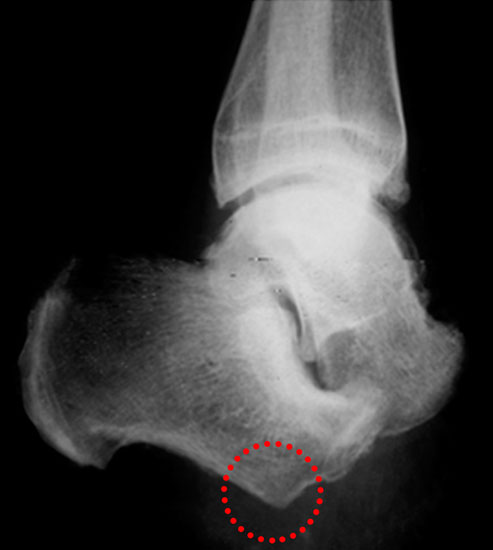

Kalkaneusteilamputationen, Kalkaneusresektion

Indikationen

• Weichteildefekte, die weder konservativ noch plastisch-chirurgisch zu decken sind,

• Lokale Osteomyelitiden mit Knochennekrose und Weichteilbeteiligung (Abb. 50).

Das Ausmaß der Knochenresektion ergibt sich aus der Defektgröße bzw. aus der Ausdehnung der Osteomyelitis 3 (Abb. 52). Eine totale Kalkanektomie ist problematisch, weil danach die Leitungsbahnen unmittelbar dem Körpergewicht ausgesetzt sind.